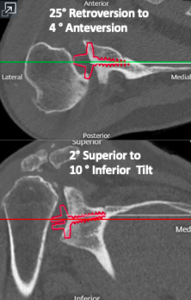

Case one is a 58-year-old male who is an avid golfer with long standing right shoulder pain. Surgical history includes previous Bristow procedure 30 years prior. Current Subjective Shoulder Value (SSV) is 30% and pain is 8/10 at baseline. Active range of motion was 110° of forward flexion, -10° of external rotation and interna rotation to the lateral buttock. Radiographs (Figure 1) and computed topography (CT) scan (Figure 2) show retained implants with loss of joint space, glenoid retroversion, and significant posterior humeral head subluxation. The patient had failed conservative management and was indicated for arthroplasty. Due to significant posterior bone loss and retroversion, an augmented anatomic component was selected for this patient. Radiographs at one year show a well seated glenoid component with restoration of the joint line and a centered humeral head (Figure 3). At five years, SSV had improved to 95% with excellent clinical motion (Figure 4).